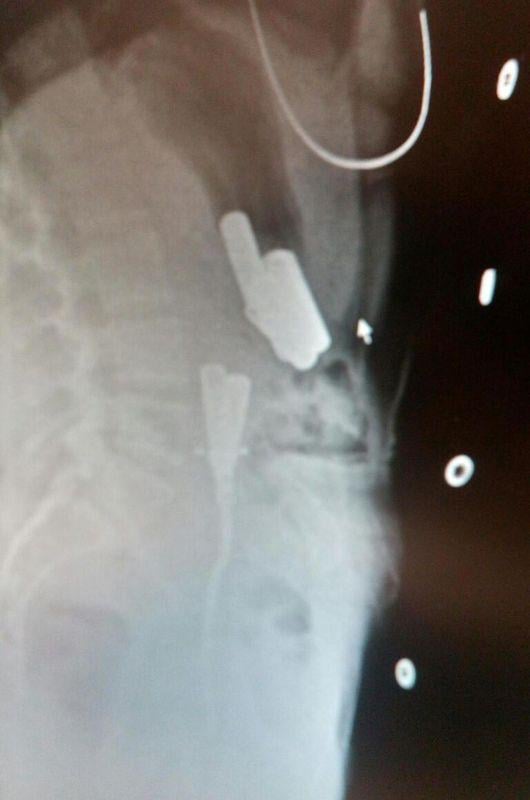

Düzce Üniversitesi Araştırma ve Uygulama Hastanesi'nde tedaviye alınan K.A.'nın röntgeni çekildi.

Doktorlar, psikolojik sorunları olan genç kızın karnındaki pilleri görünce şaşırdı. Röngende vücudunda 8 kalem pil olduğu görülen K.A.'nın tedavisi devam ediyor.